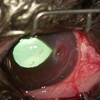

黒色壊死部周囲の血管新生、角膜浮腫あり、穿孔、眼房水流出の可能性あり。

治療は角膜深部まで到達してる可能性があるため、外科治療を選択。

角強膜移動術を行う予定です。

黒褐色〜黒色病変が角膜中央に見られることが多い。また病変は角膜実質浅層に見られることが多いが、進行すると全層に及ぶ場合がある。

病変物周囲の角膜潰瘍、角膜浮腫、血管新生、炎症産物浸潤、眼痛、眼瞼痙攣、流涙、角膜穿孔など